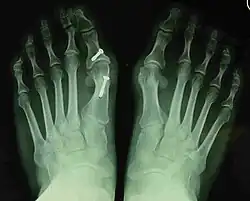

Fig. 8a. Painful hallux valgus and metatarsus primus varus deformity recurrence of left foot after osteotomy surgery

1. For recurrence correction after osteotomy procedure (Fig. 8)

Late deformity recurrence can happen after osteotomy (bone-breaking) procedures because osteotomy surgeries do not specifically stabilize first metatarsal bone.